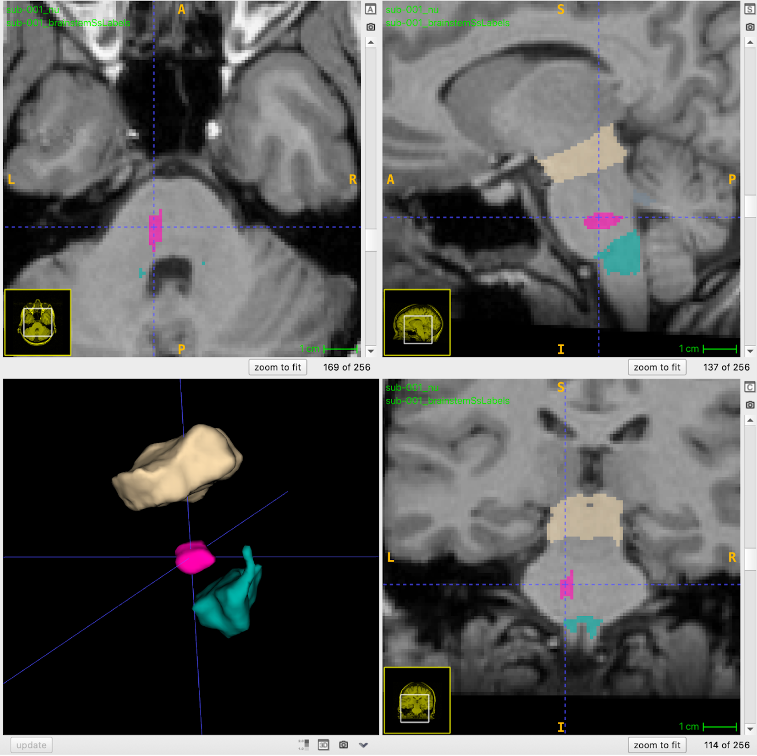

current work Neural basis of Behaviour Change in Sustainable Decision-making fMRI, Econometric, Neuroeconomics Semi-automated Anatomical Segmentation and Voxel-based Morphometry of Cranial Nerve Brainstem Nuclei from T1-w MR Images sMRI, brainstem, segmentations Neural correlates of Visual / Auditory Statistical Learning and Reading Processes fMRI, Learning, Reading previous work Increased Attention and Effect of Comprehension Check on Confirmation Bias with Belief-confirming Evidence attention, confirmation bias, belief Anxiety reduces Dishonesty in Low Trait Anxious Individuals: EEG Study P300 ERP, Broken Promise Trust Game